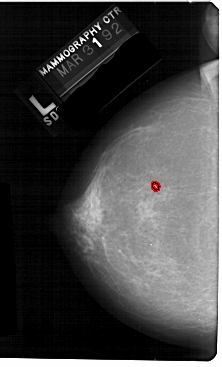

A_1599_1.LEFT_MLO

LEFT_MLO LINES 5491 PIXELS_PER_LINE 3271 BITS_PER_PIXEL 12 RESOLUTION 43.5 OVERLAY

FILE: A_1599_1.LEFT_MLO.OVERLAY

TOTAL_ABNORMALITIES 1

ABNORMALITY 1

LESION_TYPE CALCIFICATION TYPE PLEOMORPHIC DISTRIBUTION CLUSTERED

ASSESSMENT 4

SUBTLETY 1

PATHOLOGY MALIGNANT

TOTAL_OUTLINES 1

BOUNDARY